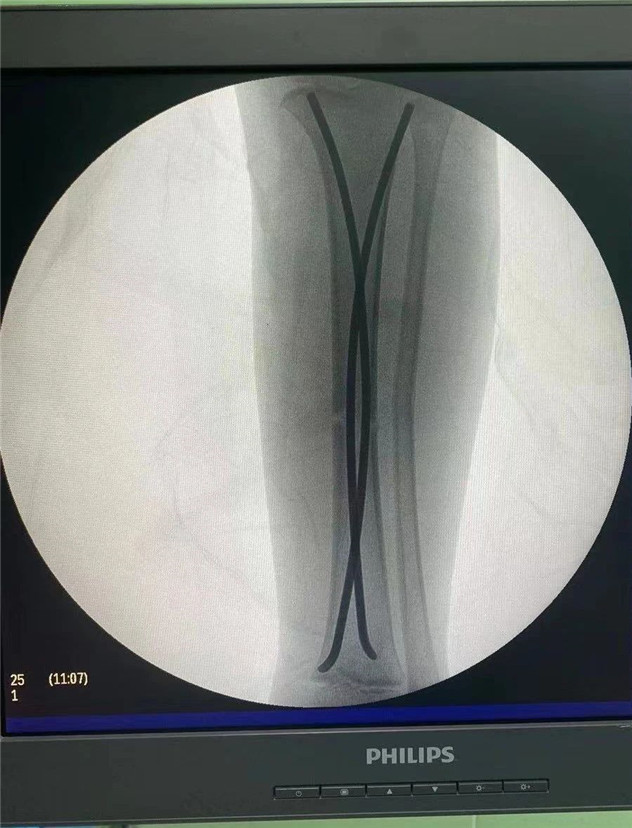

術(shù)中

2020年10月5日,在完成術(shù)前檢查后,睿睿接受了閉合復(fù)位彈性釘內(nèi)固定術(shù),手術(shù)由羅軍主任主刀。術(shù)中只需要兩個1厘米的小切口,精準(zhǔn)微創(chuàng),僅一個小時,手術(shù)便圓滿完成。